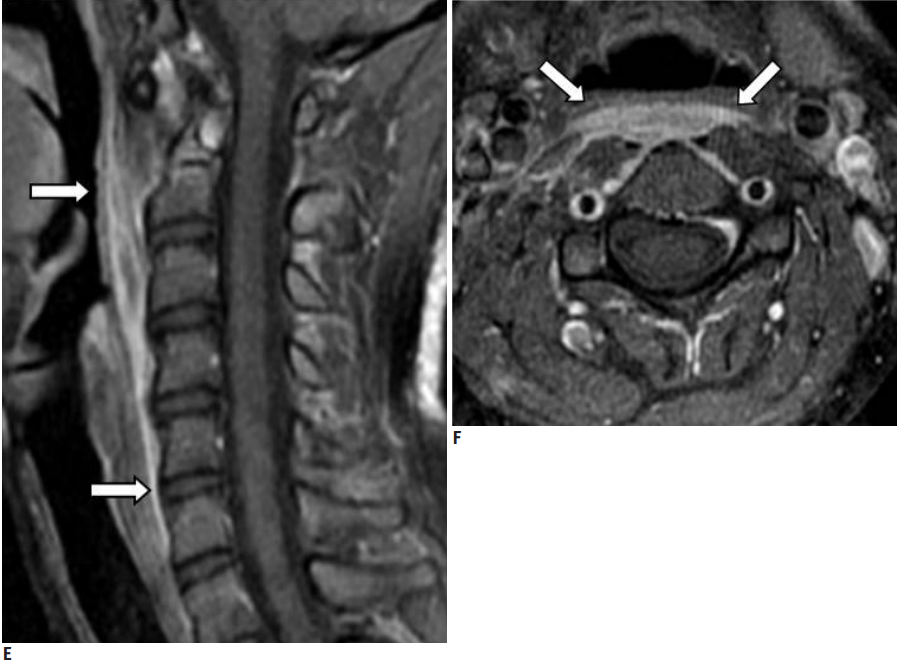

图:C2-3儿童颈椎间盘钙化合并后纵韧带骨化虽然本病可以发生在从新生儿到青春期, 但其发病高峰为6~10岁,男性多于女性,发病部位以颈椎间盘最为多见,胸椎次之,腰椎最少,颈椎中以C6-7和C3-4节段最为常见。一般为单一节段的椎间盘钙化,少数病例也可有两个部位的椎间盘钙化,部分病例可伴有后纵韧带骨化。另外,部分病例可出现神经刺激症状,且在影像检查中不仅可以看到椎间盘异常征象,还可显示肿块侵入椎管,甚至压迫脊髓,特别是合并后纵韧带骨化的病例,椎管侵占率往往大于50%。

图:患者8岁,女孩,因严重颈部疼痛、活动受限伴左上肢无力、麻木不适2天就诊。既往有锁骨骨折、额部软组织挫伤病史。查体:颈椎活动受限,左上肢肌力正常,但感觉减退。白细胞、血沉、CRP升高。颈椎侧位片和CT平扫提示C6-7椎间盘钙化(粗箭头)和后纵韧带骨化(细箭头),颈椎MRI提示C6-7水平脊髓明显受压。给予颈椎制动、枕颌带2.5kg颈椎牵引2周。随后,颈托固定1个月。2年后随访复查颈椎CT如下图,同时上述症状完全缓解。

图:2年后复查CT示C6-7钙化的椎间盘和后纵韧带骨化都消失了